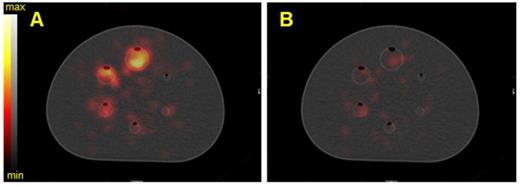

Figure 7

SPECT/CT fusion of the NEMA phantom acquired on the Optima 640 (GE) with the MEGP collimator. The phantom spheres were filled with 35 kBq/mL of 225Ac. A) Reconstructed image of the 217.5 keV ± 8% emission window without scatter correction, B) Reconstructed image of the 217.5 keV ± 8% emission window with scatter correction.

Theranostics Image